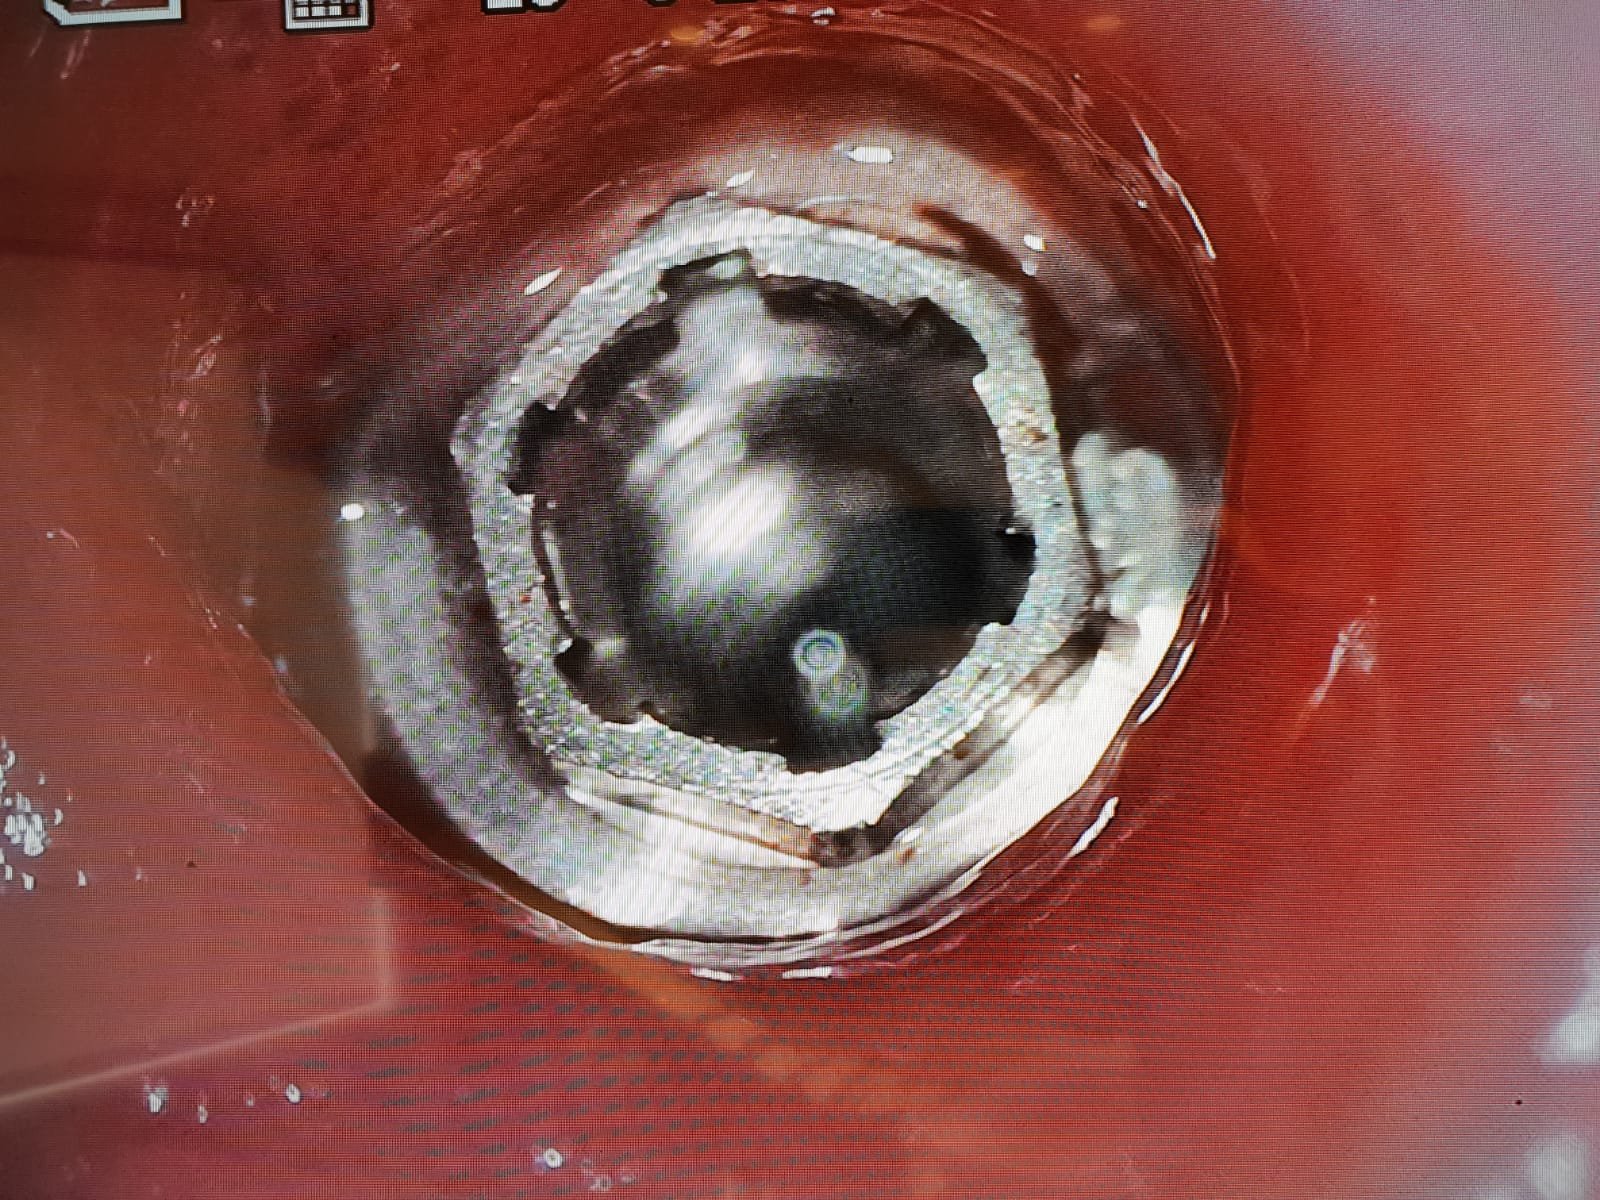

Buenas tardes, envío fotos de implantes colocados hace 10 años en Menorca. Es un hexágono externo con unas muecas internas. Envío fotos a ver si alguien nos puede decir que [...]